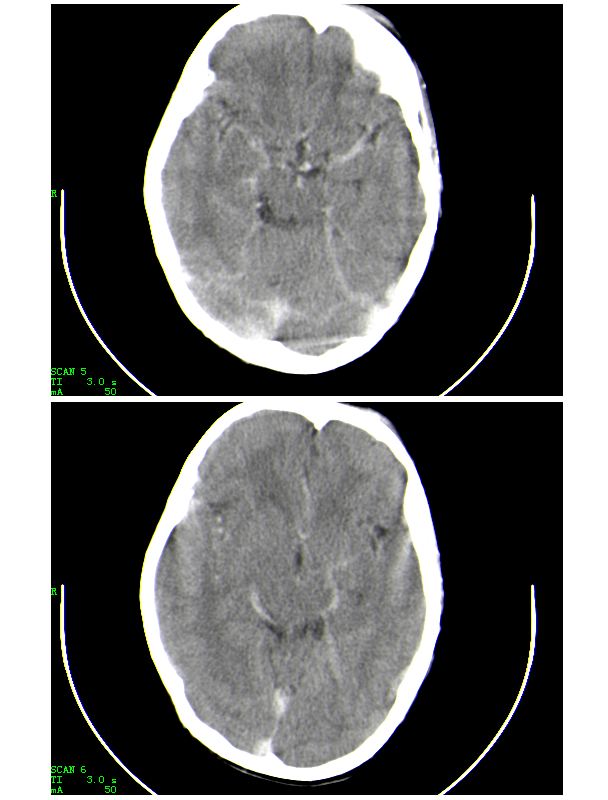

男,13岁,头部外伤后头痛、呕吐三小时就诊,查体,见小孩精神状态尚可,面部,嘴唇青紫明显,后作心脏彩超证实为“发四”,有复查片,大家先看看首诊片,考虑什么

感谢大家的关注,本例我们最后诊断为高血红蛋白症所致的脑血管改变,患者血红蛋白258g/l

下面是第二天的复查和受伤后第五天的复查,左侧硬膜下血肿有所吸收,脑内条状高密度无改变